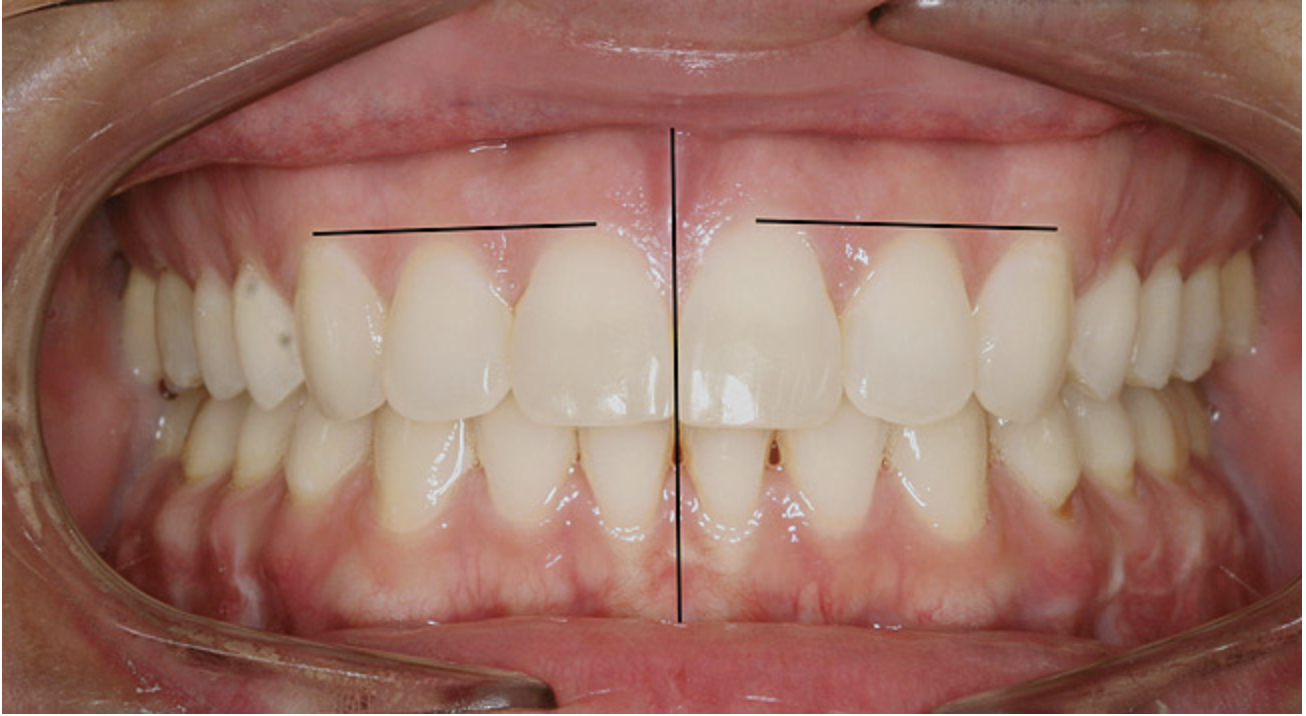

Figure 8  Intraoral view of the occlusion of patient from Figure 7 after retreatment. The occlusion is adequate to finish with equilibration.

Figure 8

Figure 7C This case is an example of the importance of evaluating the bite with the joints seated in a stable position. Orthodontic treatment was rendered to correct a "deep overbite" and trauma to the maxillary incisors. C) Models mounted in CR after use of a superior repositioning splint to stabilize the joints. With stabilized joints, the true malocclusion is uncovered. The patient went back into orthodontic treatment and required mandibular advancement surgery.

Figure 7C

A stable TMJ is critical in establishing a normal functional occlusion. Unless the condyles are in a stable musculoskeletal position, there are always interferences to normal function and stress placed on the masticatory system.1-3,15 In orthodontics, the Angle classification of malocclusion using handheld models has been the standard to evaluate the fit of the teeth. However, it is not possible to truly identify the occlusion/malocclusion using handheld models. Before the occlusion can be evaluated, the clinician must ascertain the joint position and condition (Figure 7 and Figure 8).1,16